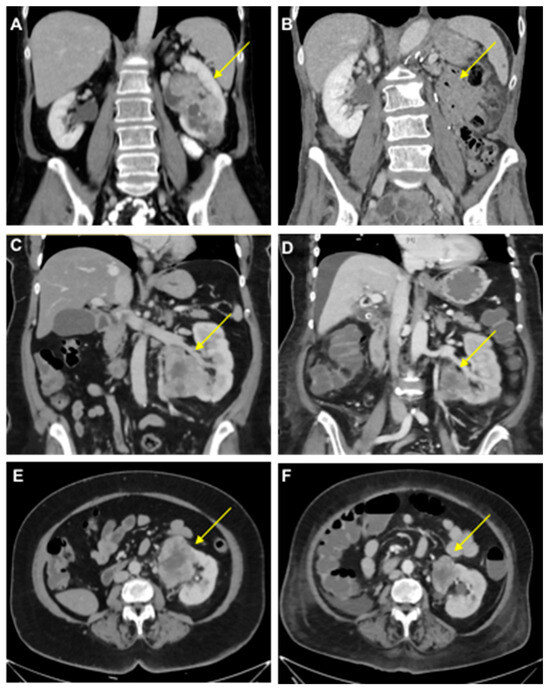

- Case study 1:

- Case study 2: